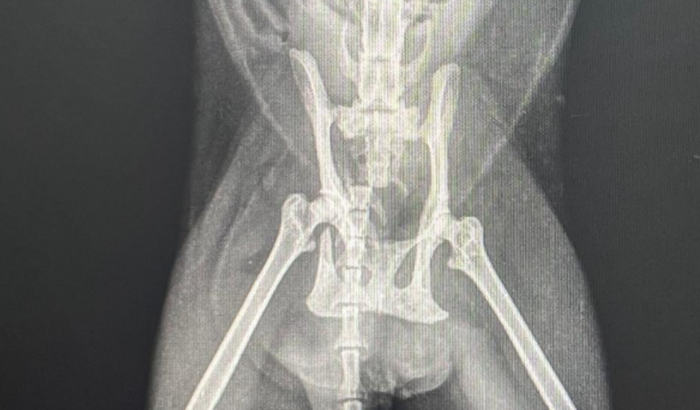

Oi pessoal, me chamo Ana Júlia na noite do dia 09/01/2025 quinta-feira a gata da minha cunhada estava saindo no portão de casa sentido a rua quando um rapaz de moto atropelou ela sem prestar nenhum socorro ou suporte e saiu correndo com a moto a gata foi se arrastando pra dentro de casa como ela podia levamos ao veterinário 24h onde foi feito raio x e a descoberta que ela quebrou a coluna e quebrou a bacia estamos agora em busca de ajuda pra fazer essas duas cirurgias da coluna e bacia fora a internação e medicamentos infelizmente na rua da nossa casa não tinha nenhuma casa com câmera pra localizar a placa do motorista então contamos com a ajuda de todos em nome de jesus que Deus abençoe a cada um que puder contribuir nessa ação pra nossa princesa